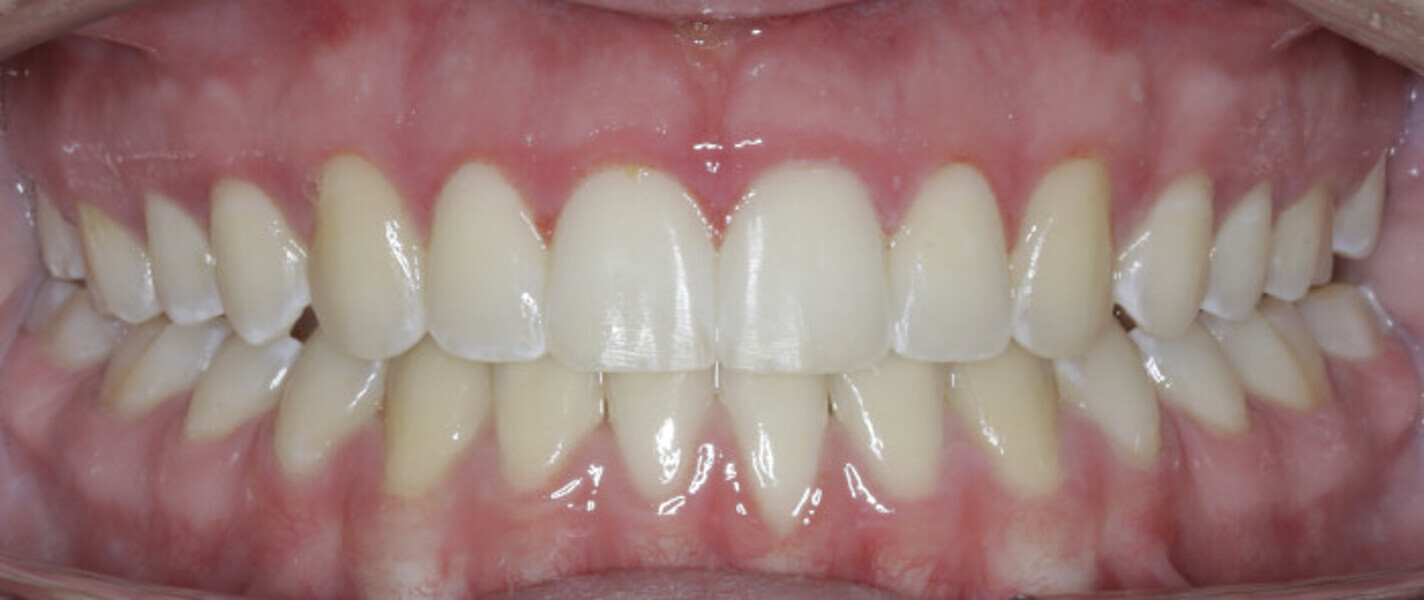

New Age orthodontics and orthopaedics with temporary anchorage devices